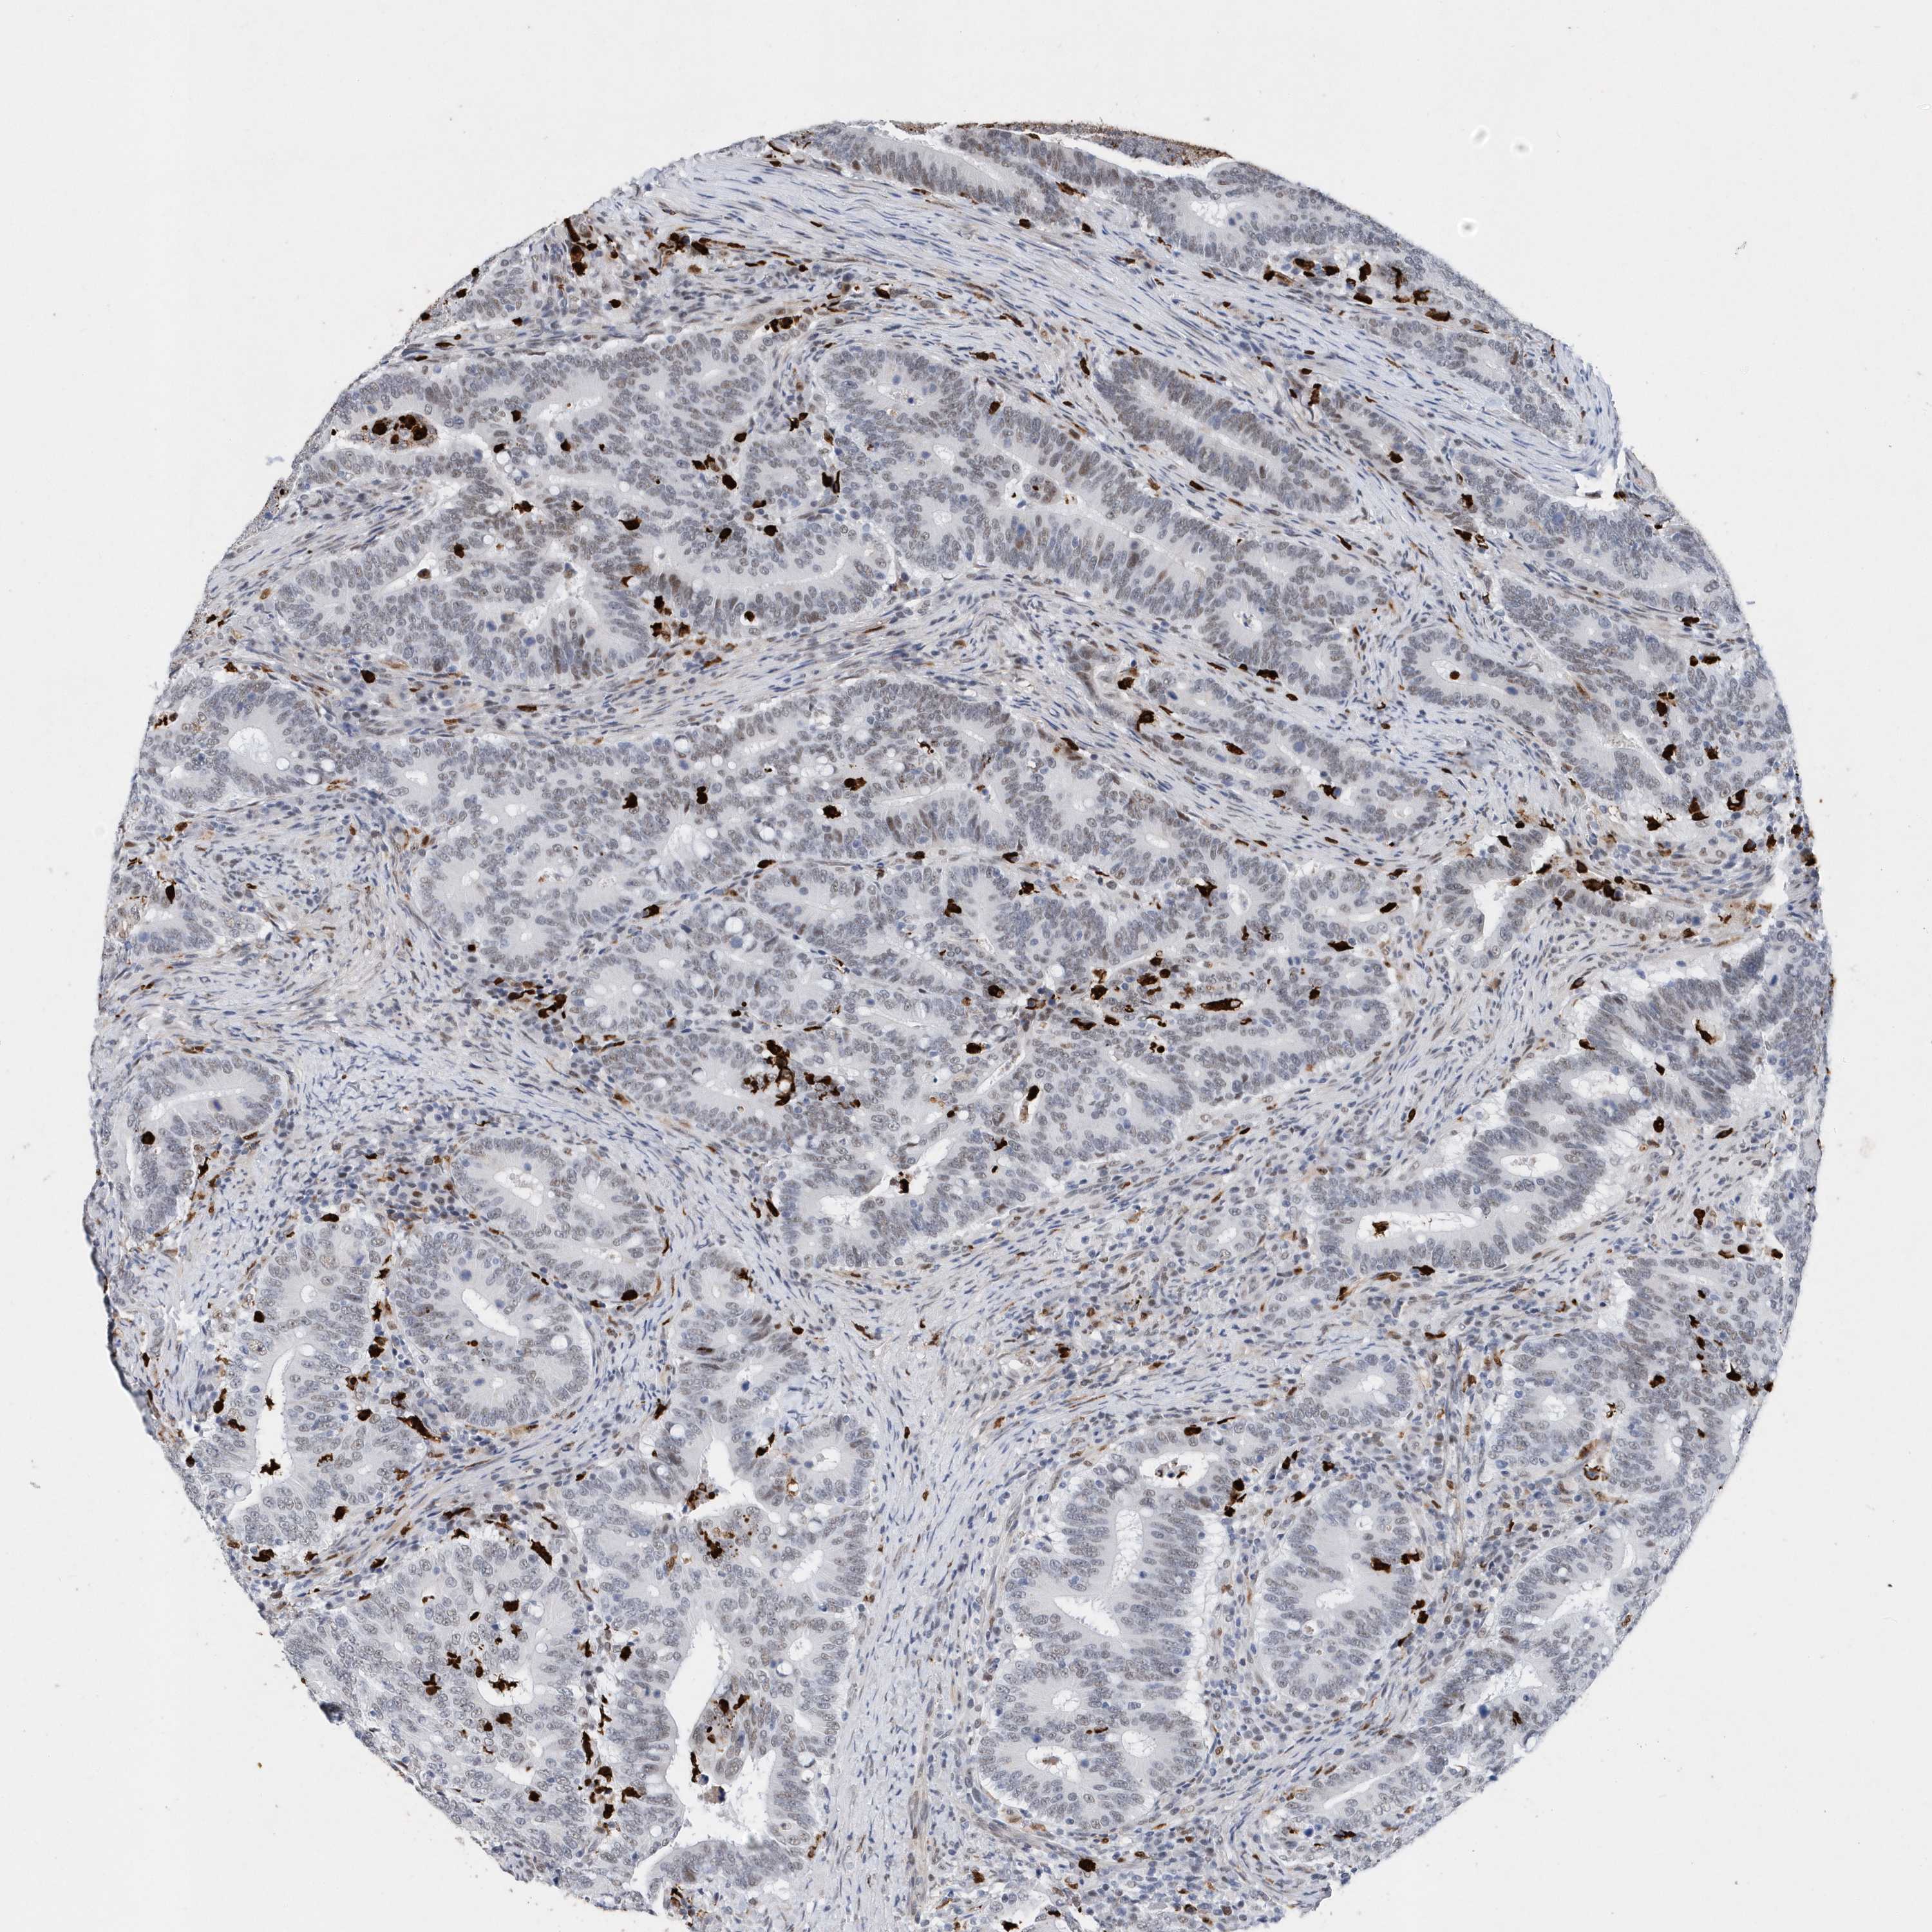

CANCER COLORECTAL CANCER Show tissue menu

Colorectal cancer

Human cancer

Colon adenocarcinoma